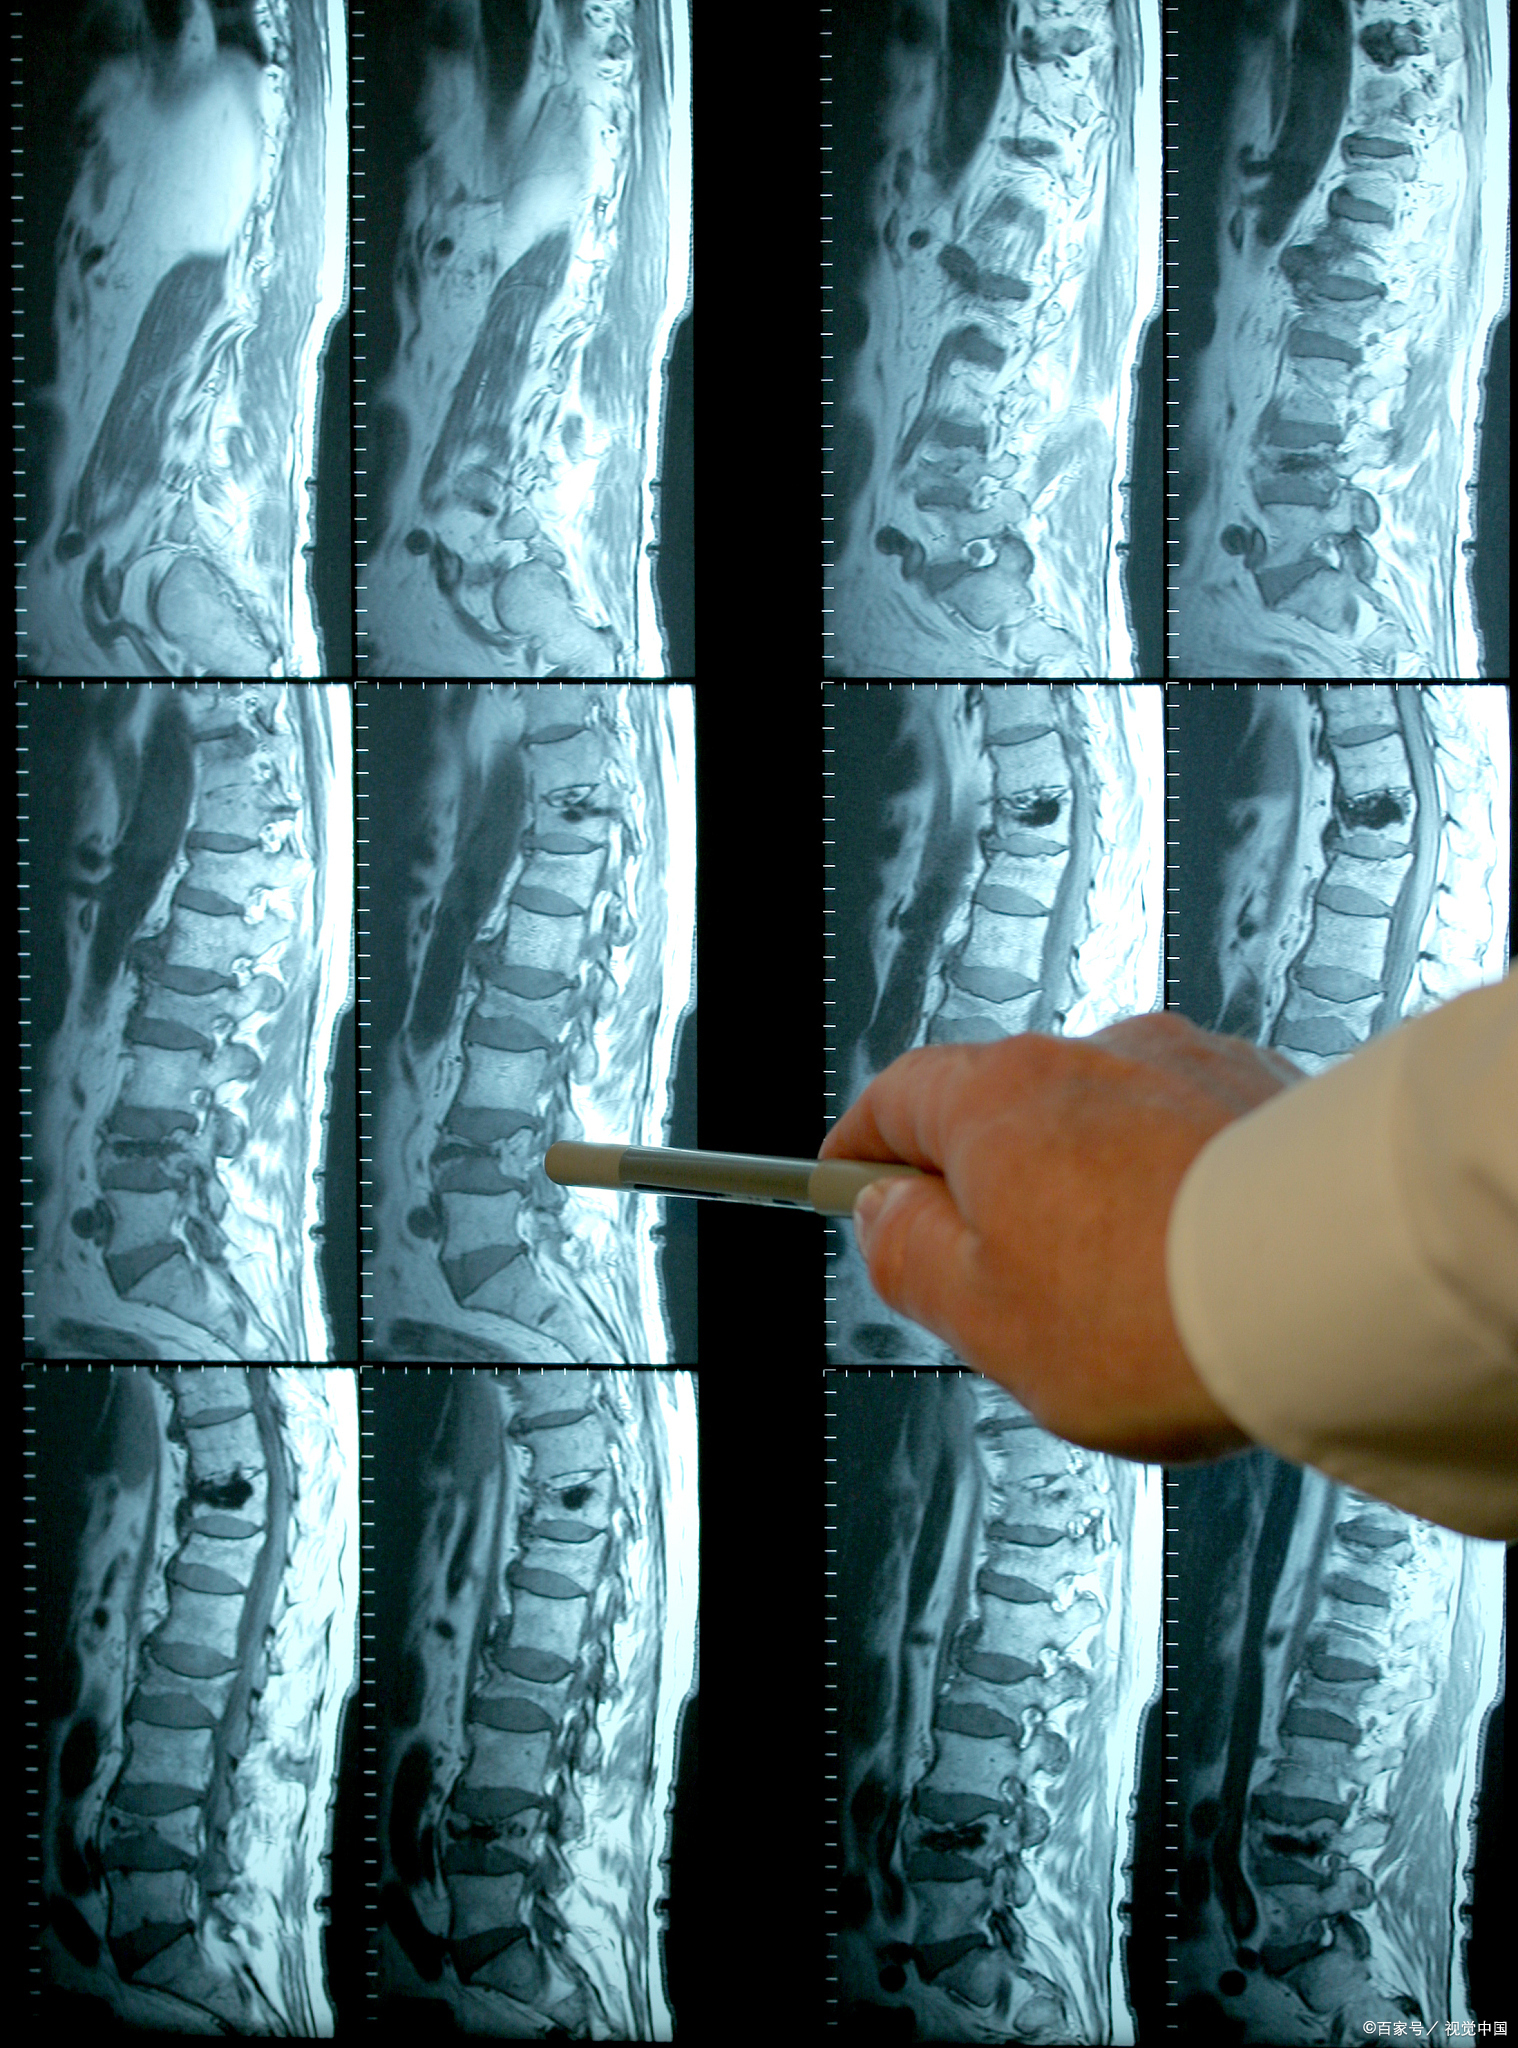

通过详细沟通了她的情况,并查看了相关报告,本身腰椎间盘突出的并不严重,主要是软组织损伤,加上本身气血虚,水肿和炎性代谢不断压迫和刺激神经,并且吃的药不够对症,症状得不到缓解,目前还处于急性期。我建议她继续卧床,但可以适当卧床锻炼,然后针对她的气血不足,肾阳虚来辨证开方,采用通经活络,活血化瘀来综合调理。服用两周半,可以下地活动,症状得到很大改善。